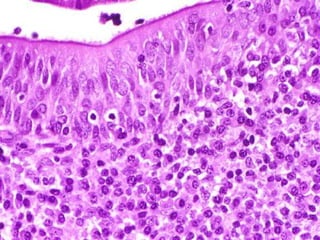

De naturaleza linfoepitelial, es el unico organo linfatico lobulado,

alcanzando su maximo desarrollo cerca de la pubertad, cuando puede

pesar de 35 a 40 gramos.

Despues de los primeros años de vida empieza a involucionar (atrofia)

y se infiltra de adipocitos. Sin embargo, su funcion pede continuar

incluso en adultos de mayor edad.

No tiene nodulos ni senos linfaticos y se extiende de la raiz del cuello

a la parte superior del torax, situado en el mediastino superior.

Corteza:

Medula:

Contiene linfocitos pequenos denominados Timocitos. Estos son

celulas de coloracion

Oscura que se originan por division de celulas madre que

originalmente emigraron al

Timo procedentes de la medula osea. Estos ocultan las celulas

reticulares epiteliales.

Se tine mas clara y es menos compacta que la corteza, y en

consecuencia las celulas

reticulares epiteliales son mas notables. La caracteristica mas

notables del timo son

Los corpusculos timicos o de Hassal.

corpusculos timicos o de Hassal: Estructura esferica y acidofila con diametro

que varia, de 20 a mas de 100 micras. Las celulas centrales son grandes y pre-

Sentan signos de hialinizacion y calcificacion.